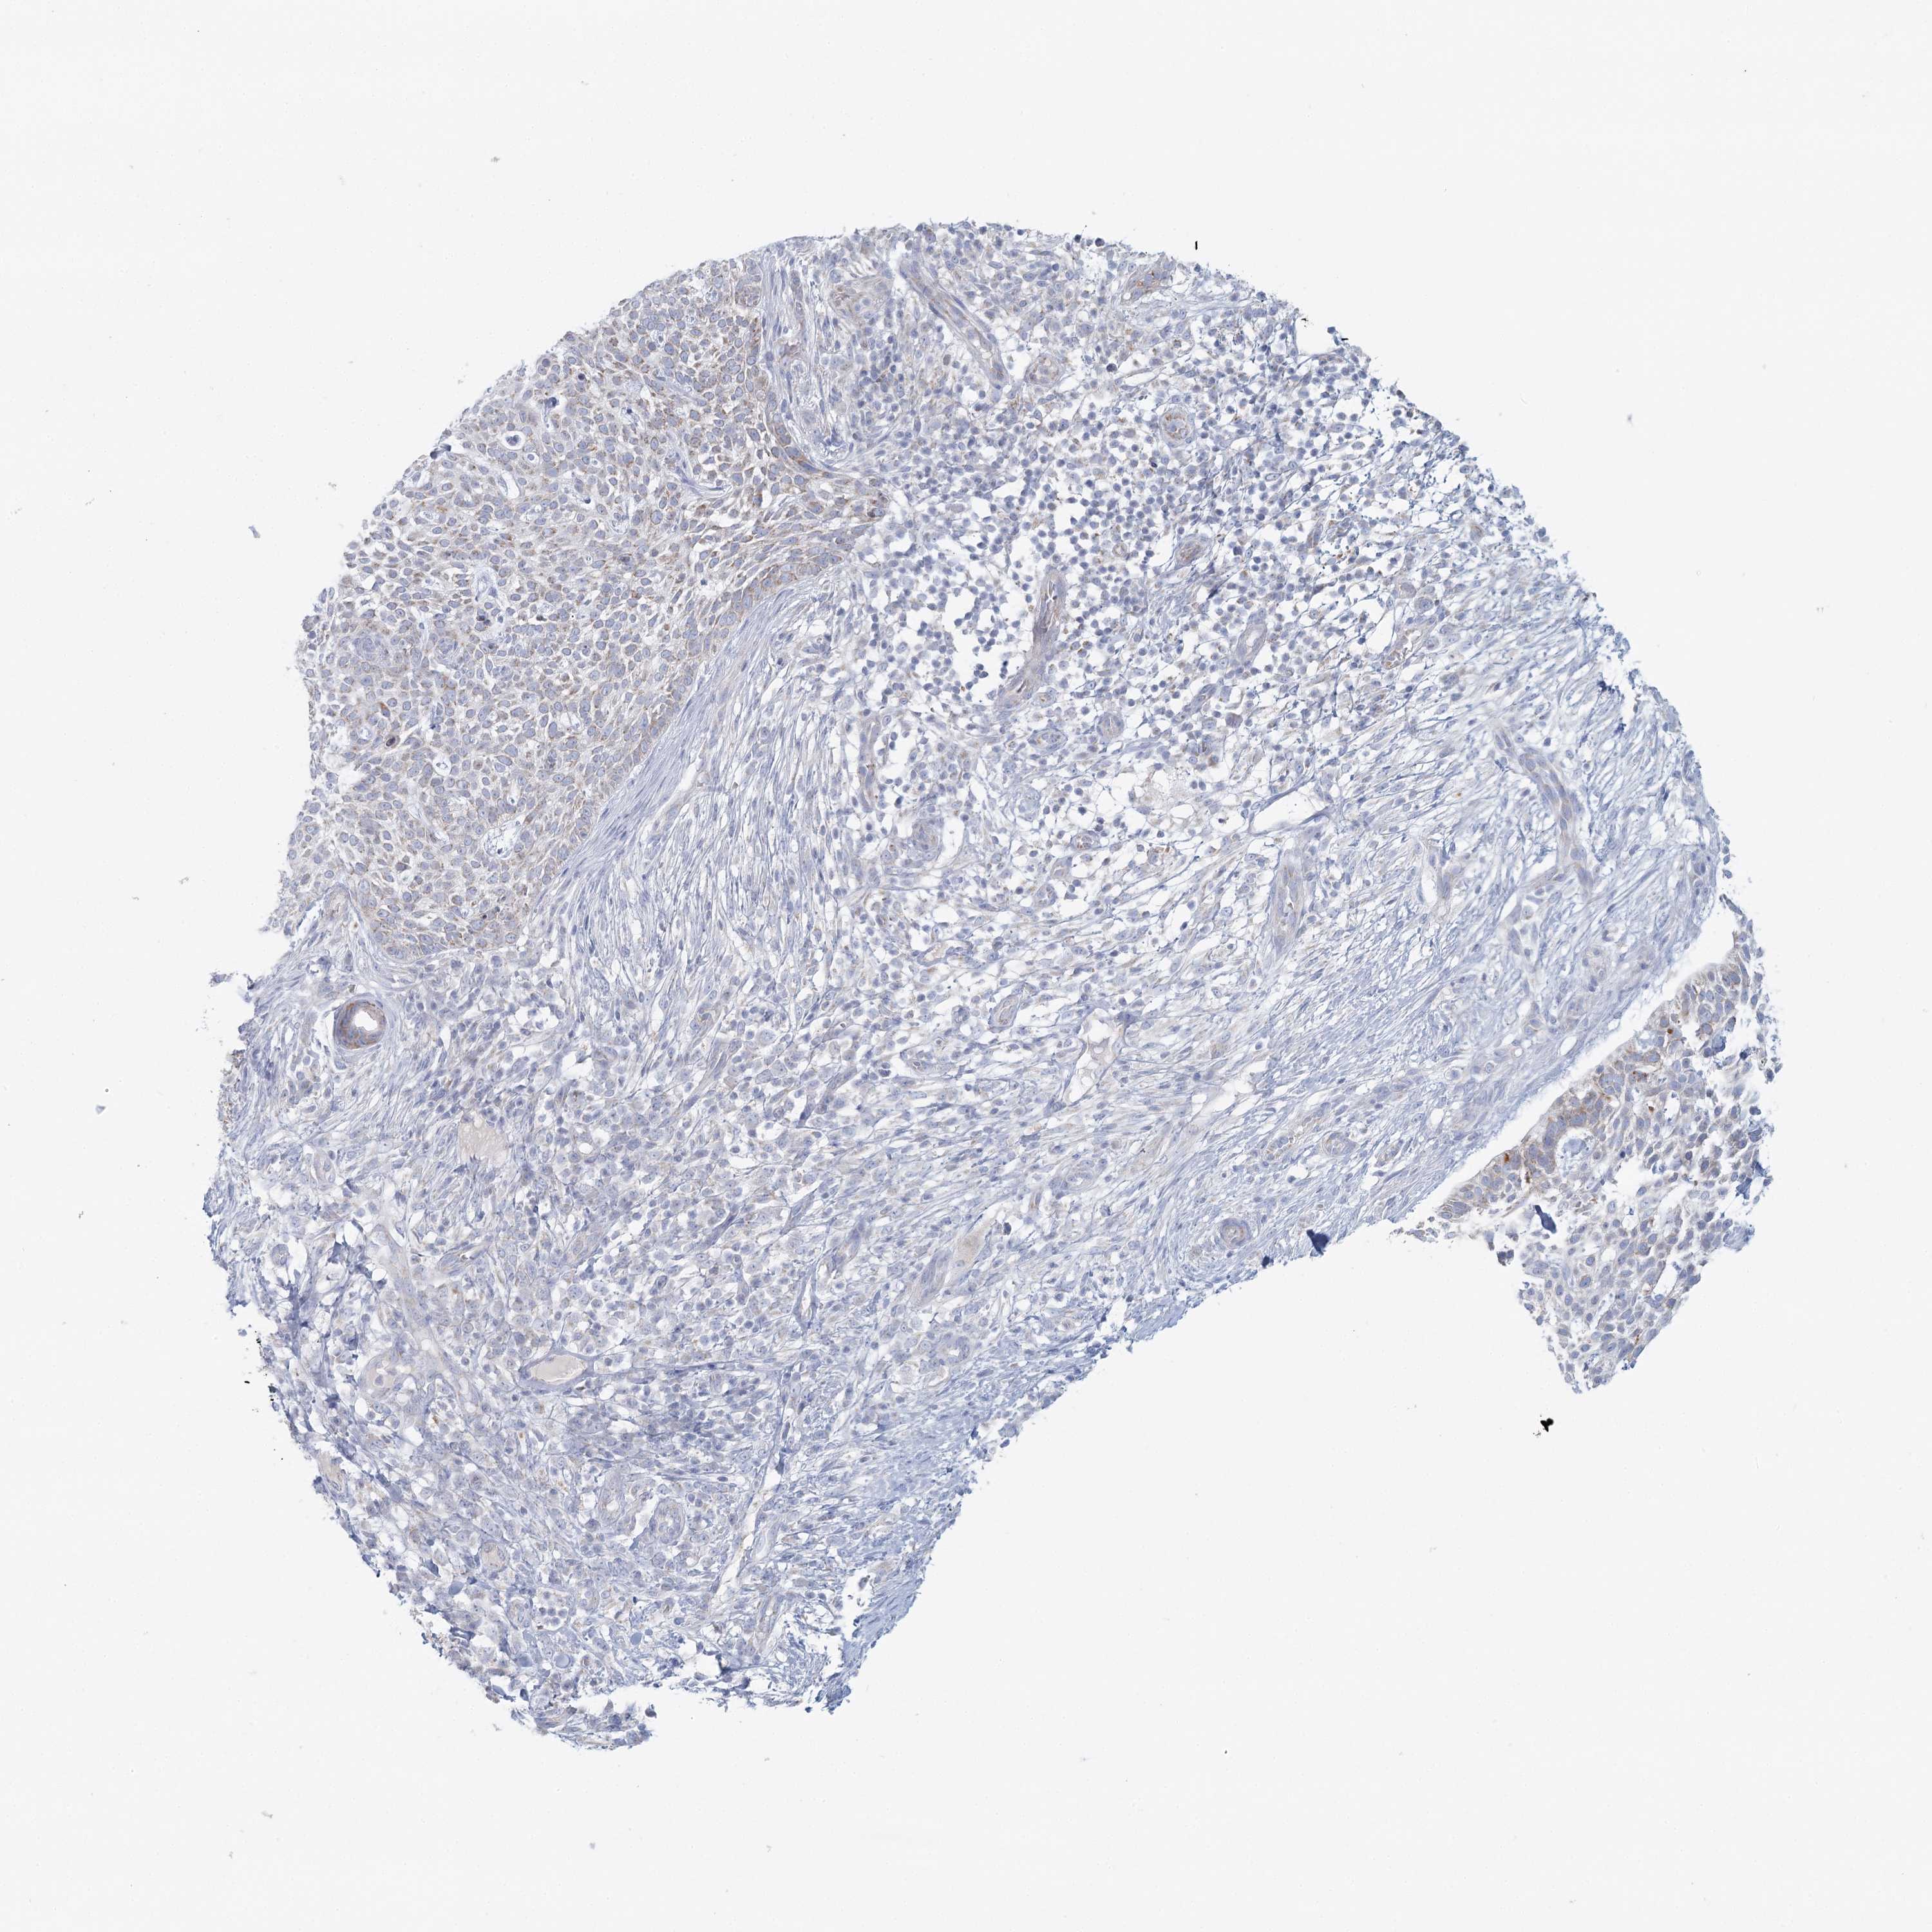

Basal cell and squamous cell cancer

SKIN CANCER - Protein expressioni

A mouse-over function shows sample information and annotation data. Click on an image to view it in a full screen mode. Samples can be filtered based on level of antibody staining by selecting one or several of the following categories: high, medium, low and not detected. The assay and annotation is described here.

Antibody stainingi

Antibody staining in the annotated cell types in the current human tissue is reported as not detected, low, medium, or high, based on conventional immunohistochemistry profiling in selected tissues. This score is based on the combination of the staining intensity and fraction of stained cells.

Each image is clickable and will lead to virtual microscopy that enables deeper exploration of all samples and also displays staining intensity scores, fraction scores and subcellular localization as well as patient and tissue information for each sample.

Antibody HPA036752

Antibody HPA036753

Staining

Not detected

Negative

None

Basal cell carcinoma